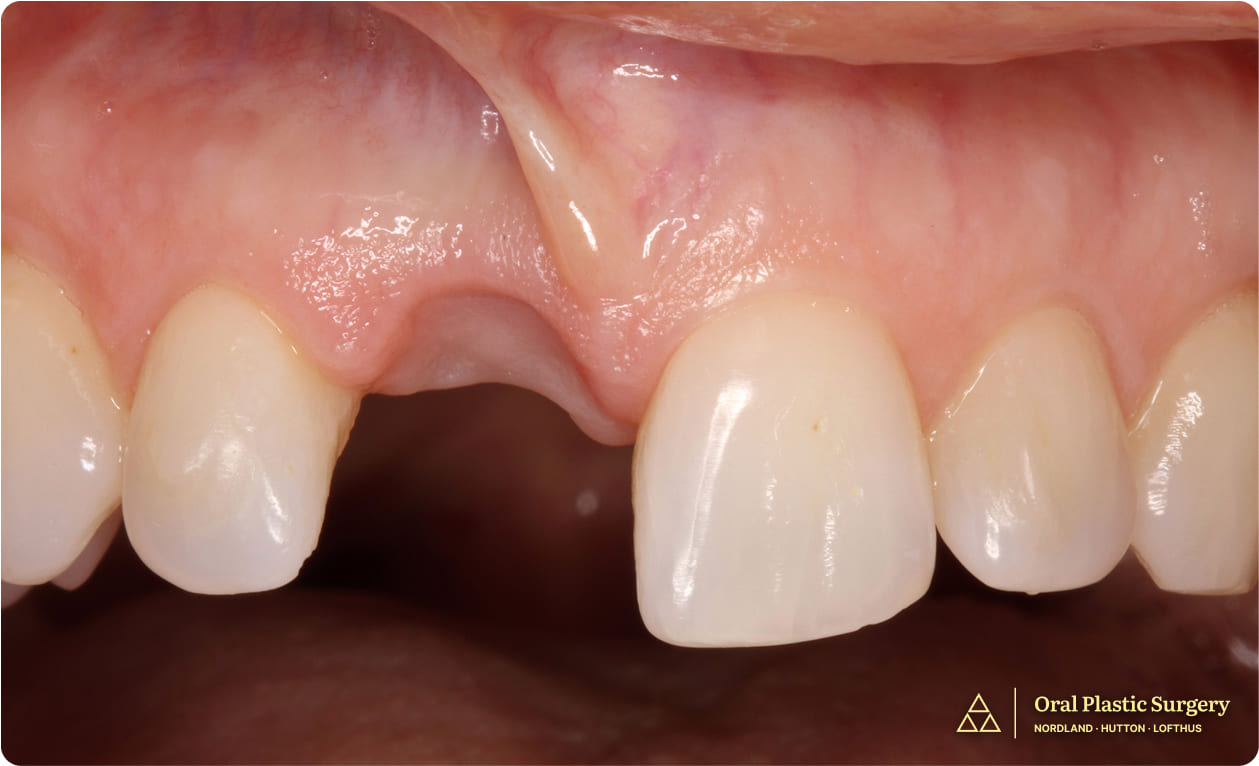

This sudden break left Marianne in both a physically and emotionally difficult position.

Her central front tooth—a focal point of her smile—was deemed non-restorable, and the idea of a visible prosthetic or complex replacement filled her with concern.

Tooth #8 shows a visible fracture, indicating structural compromise and the need for further evaluation and treatment